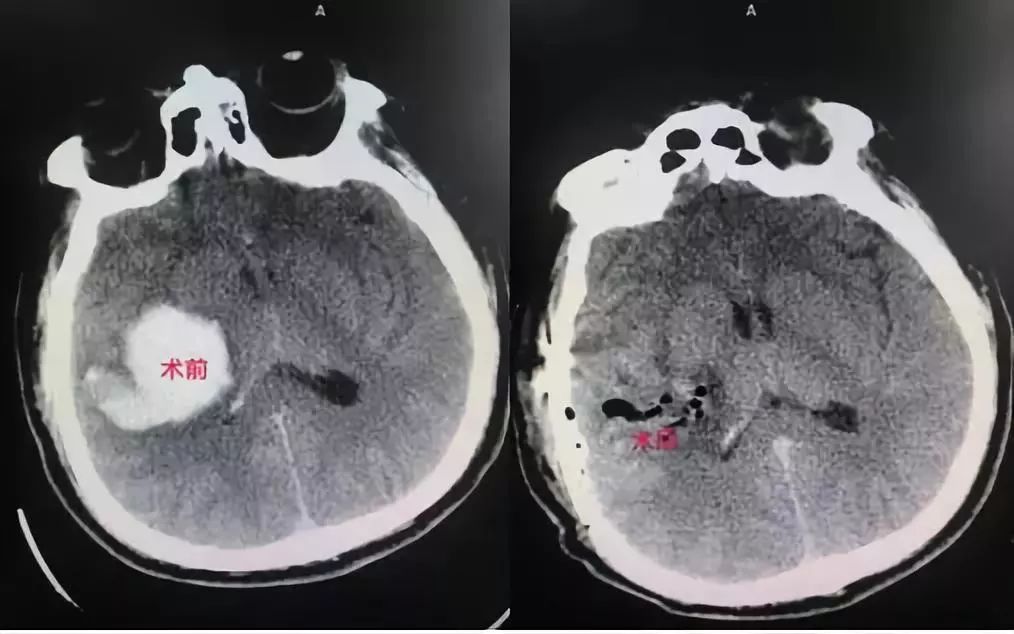

比如我们改良传统的“脑出血”去骨瓣减压颅内血肿清除术,在术前术中做好充分的评估,尽可能做到小骨窗微创清除、一期还纳骨瓣,免去了原来需要行二期颅骨修补的必要,最大程度较少患者的损伤和经济压力。